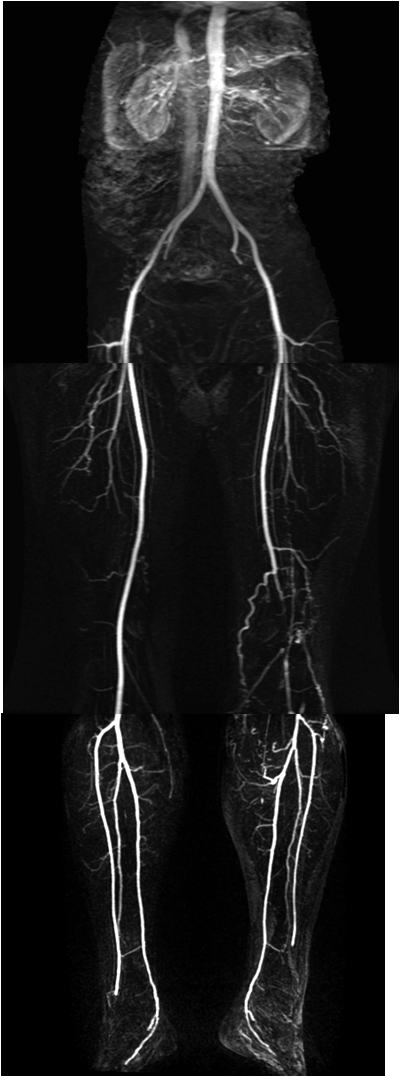

Image

Proximal aortic occlusion – Leriche’s syndrome

Bilateral multiplex femoral artery stenosis

Fig. 20., 21.: DSA examination in lower extremity obliterative arterial disease

Contrast enhanced MR angiography"

Fig. 22. Left sided segmental occlusion at the iliofemoral segment

CT angiography

Fig. 23. Bilateral superficial femoral artery occlusion with collateral filling

Multi-slice CT is able to perform CT angiography scans that map the body from the diaphragm to the ankles depicting the complete arterial tree with adequate intensity and with appropriate spatial resolution. In most cases this has a sufficing diagnostic value and it is especially advantageous for the rapid assessment of patients in poor condition. For the MRA of this wide region a special table toggling technique is required. This method applies prolonged injection of intravenous bolus contrast medium, and in three table-toggling steps it can visualize the arterial system of the abdominal aorta and the peripheral arteries up to the ankle with an acceptable spatial resolution. MRA examinations has the best diagnostic value for lesions presenting at the aortoiliac and femoropopliteal regions in cases with a relatively limited extension and a reasonable severity. CTA examination (with specific contrast injection protocol) provides better spatial resolution tough even in this region starting to replace angiography as a first choice of examination in the diagnostics of acute coronary syndromes.